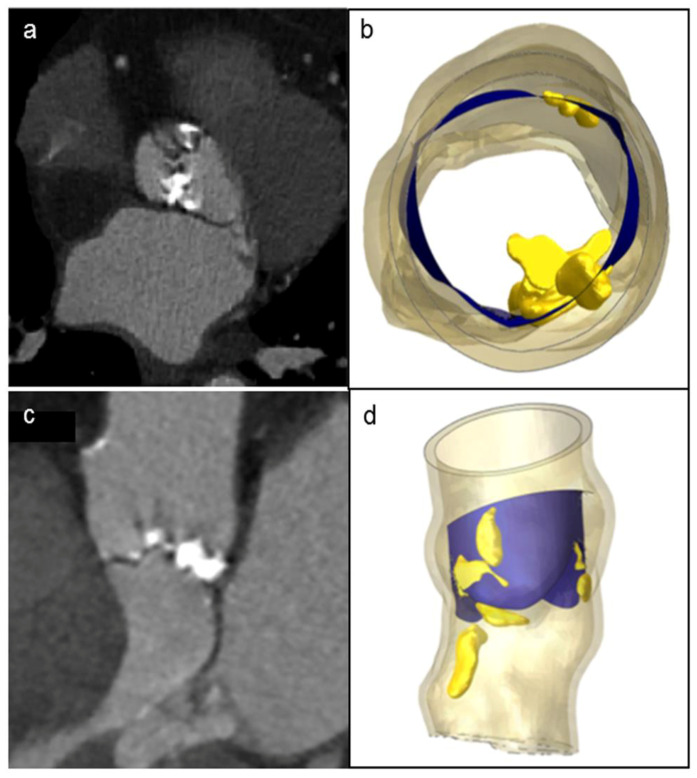

A patient-specific model of the aortic valve obtained from preoperative CT imaging is shown in Figure 2. FEA simulations of the positioning and deployment of self- and balloon-expandable devices in the two investigated patients who developed complications are depicted in Figure 3a,a′,c,c′, respectively, and compared with corresponding intra-operative images (Figure 3b,b′).

Patient’s preoperative CT scans of severe bulky calcifications attached to aortic valve leaflets and root (a,c), compared to the model reconstruction (b,d).